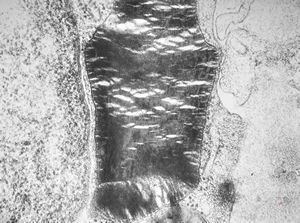

M, 2y. | globoid leukodystrophy (Krabbe disease) … n. suralis